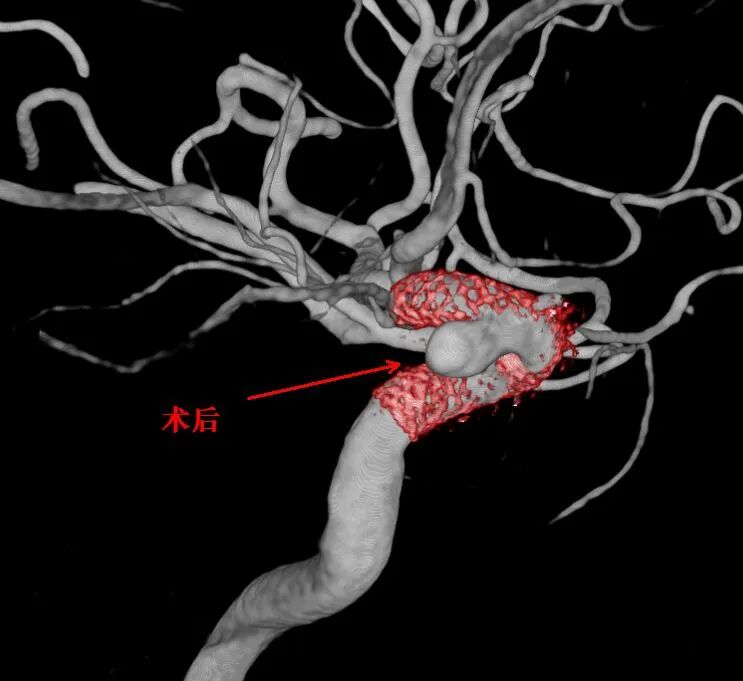

• 神经外科接力攻坚:邱耀忠主任医师、李建副主任医师携手,针对同侧的两个动脉瘤植入血流导向密网支架,隔绝血流冲击,预防破裂。

术后影像显示:脑动脉血流畅通,动脉瘤处理稳定,无出血或缺血并发症。